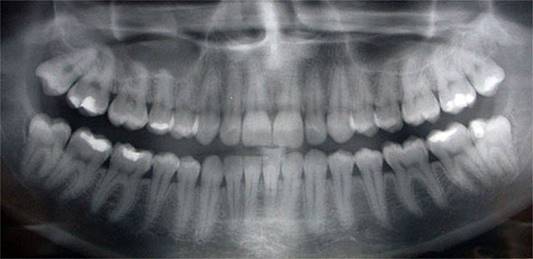

One of the key tools we use in Dental Decoding in addition to the clinical examination of the patient is the study of panoramic radiography (panoramic x-ray). We can use it to analyze several factors that are not seen with the naked eye including the shape and position of the roots of the teeth.